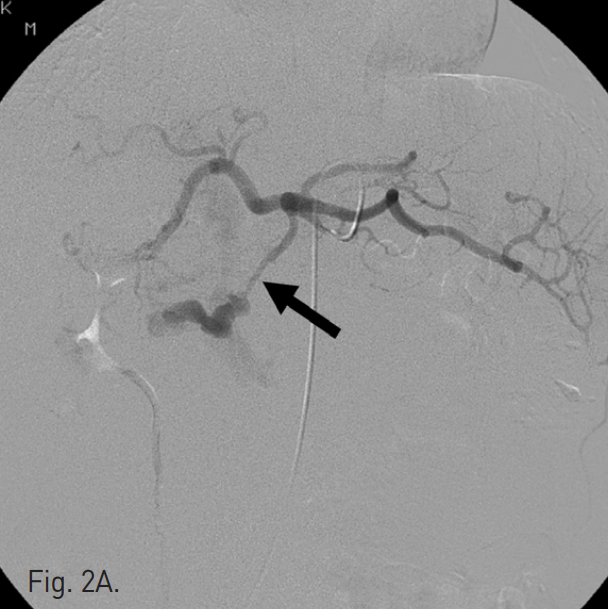

A. Celiac angiography shows a pseudoaneurysm of dorsal pancreatic artery (arrow).

초음파 및 투시 하에서 우측 대퇴동맥을 천자하고 5F Cobra catheter(Cook, Bloomington, IN, USA)를 이용하여 복강동맥 및 상장간막동맥 조영술을 시행하였다. 복강동맥 조영술에서 dorsal pancreatic artery에서 유출되는 조영제의 누출과 거짓동맥류를 확인하였고 상장간막 정맥으로의 동정맥루를 확인하였다(Fig. 2A, B). Microcatheter(Renegade, Boston Scientific, Natick, MA, USA)를 이용하여 이 거짓동맥류를 선택하였고, 10mm Interlock coil(Boston Scientific, Natick, MA, USA) 6개와, 10mm Nester coil(Cook, Bloomington, IN, USA) 3개를 사용하여 embolization을 시행하였다(Fig. 2C). 이후 남아있는 거짓동맥류와 동정맥루에 대하여 NBCA와 lipiodol mixture(3:1)를 이용하여 색전술을 시행하였다. 시술 후 동맥조영술에서 남아있는 거짓동맥류나 상장간막 정맥으로의 동정맥루는 보이지 않았다(Fig. 2D).